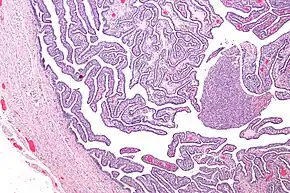

Micrograph of salpingitis – a component of pelvic inflammatory disease. H&E stain.

Upon a pelvic examination, cervical motion, uterine, or adnexal tenderness will be experienced.[5] Mucopurulent cervicitis and or urethritis may be observed. In severe cases more testing may be required such as laparoscopy, intra-abdominal bacteria sampling and culturing, or tissue biopsy.[14][21]